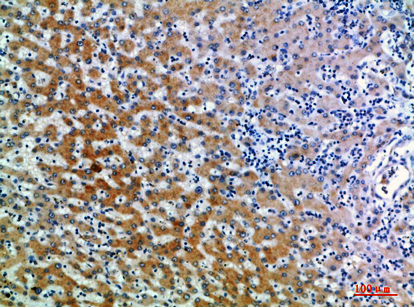

IHC-P,IF-P,IF-F,ICC/IF,ELISA

IHC-P 1:50-200, ELISA 1:10000-20000, IF-P/IF-F/ICC/IF 1:50-200